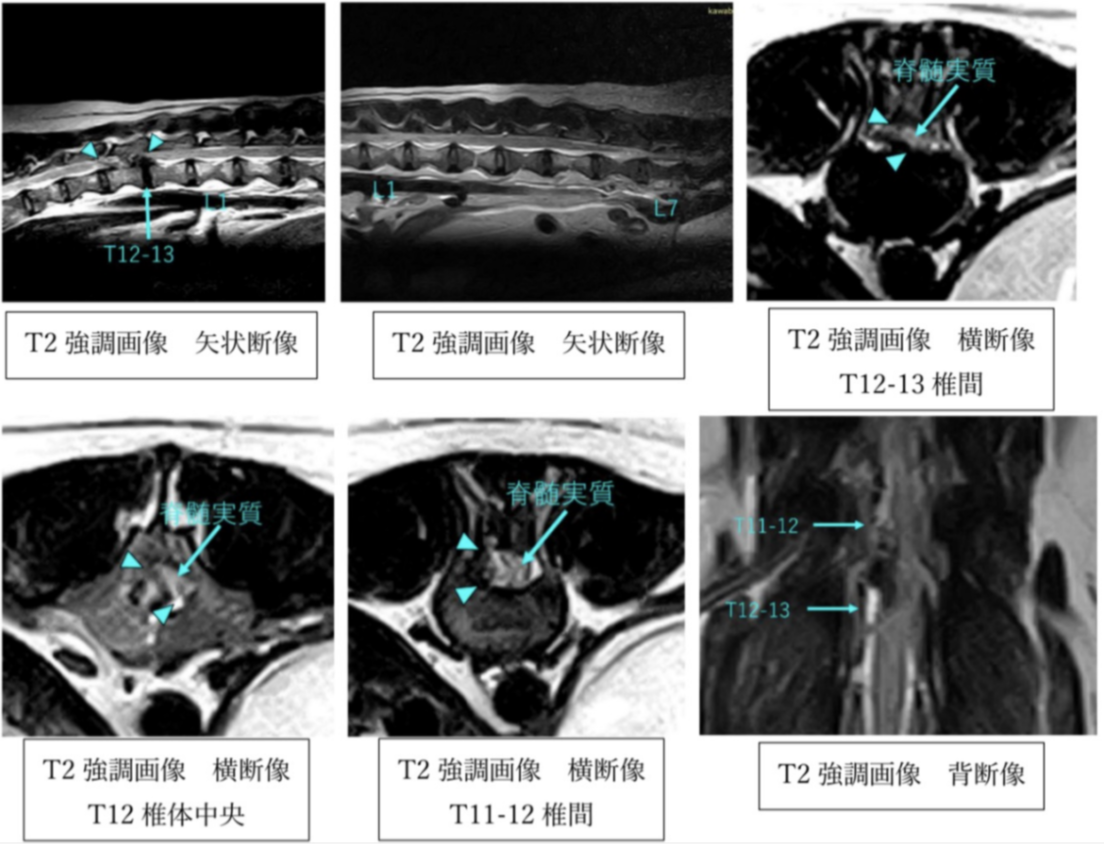

神経外科